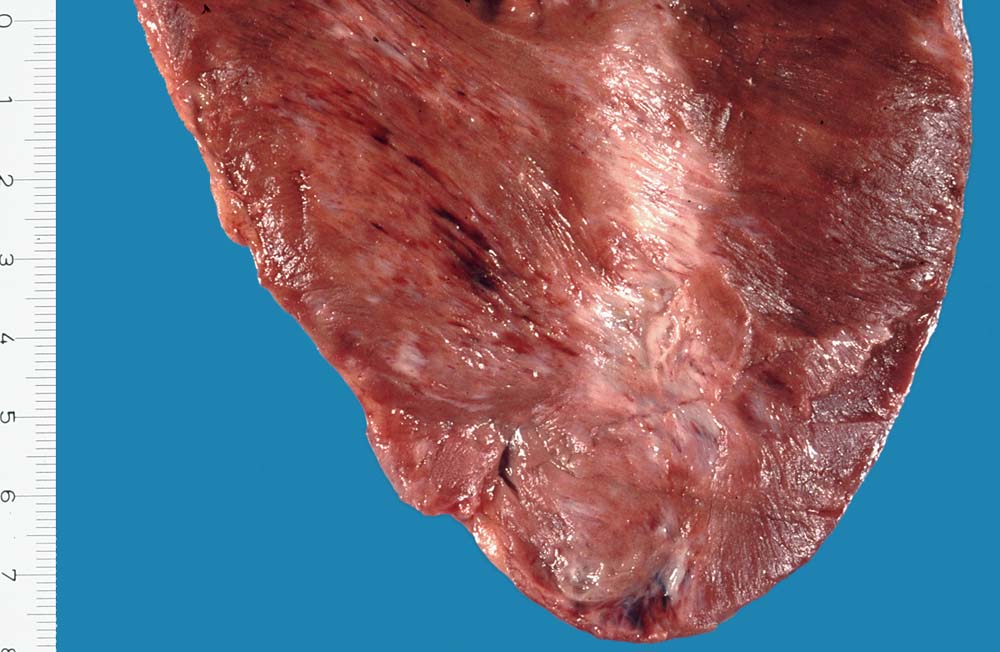

Morphologie:

Eine restitutio ad integrum nach abgelaufener Myokardnekrose ist nicht möglich. Wird das Ischämieereignis überlebt, kommt es zu einer reparativen Regeneration mit Ersatz der Muskulatur durch kollagenreiches Narbengewebe. Dieser Vorgang setzt etwa ab dem 9. Tag nach Infarkt ein und dauert bis zur vollständigen narbigen Ausheilung bei transmuralem Infarkt etwa 50 Tage. Makroskopisch imponiert die Narbe als fasriges weisses derbes Areal. Von einem Infarkt spricht man, wenn die Nekroseareale einen Durchmesser von mindestens 3cm Durchmesser haben. Ab dieser Grösse kann klinisch das Bild eines Myokardinfarktes ausgelöst werden. Kleinere, makroskopisch sichtbare Narben werden als grobfleckige Myokardfibrose (> 873) (> 234) bezeichnet.

Morphologische Merkmale:

• Herdförmiger Ersatz der Muskulatur durch zellarme rote Kollagenfaserbündel.

• Hypertrophiezeichen der Herzmuskulatur im Randbereich der Narbenareale (verdickte Herzmuskelzellen mit vergrösserten hyperchromatischen Kernen).

• Im untersten Biopsiefragment sind die Narbenareale bandförmig subendokardial verteilt. Zwischen Narbengewebe und Endokard findet sich eine schmale Schicht erhaltener Muskelzellen (Ernährung dieser Zellen per Diffusion direkt aus dem Herzblut).